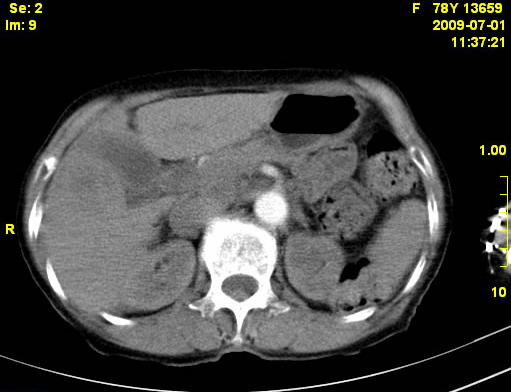

以下是引用zjzjr在2009-7-3 11:02:00的发言:[br]动脉期不均匀强化,门脉期及延迟期强化明显,肝门部见肿大淋巴结影,肝内胆管扩张.考虑肝右叶前段胆管细胞癌伴肝门淋巴结转移,胆内胆管扩张.慢性胆囊炎.

以下是引用dsl555在2009-7-4 10:59:00的发言:[br]考虑肝右叶前段胆管细胞癌伴肝门淋巴结转移,胆内胆管扩张.慢性胆囊炎. [br][br]支持。